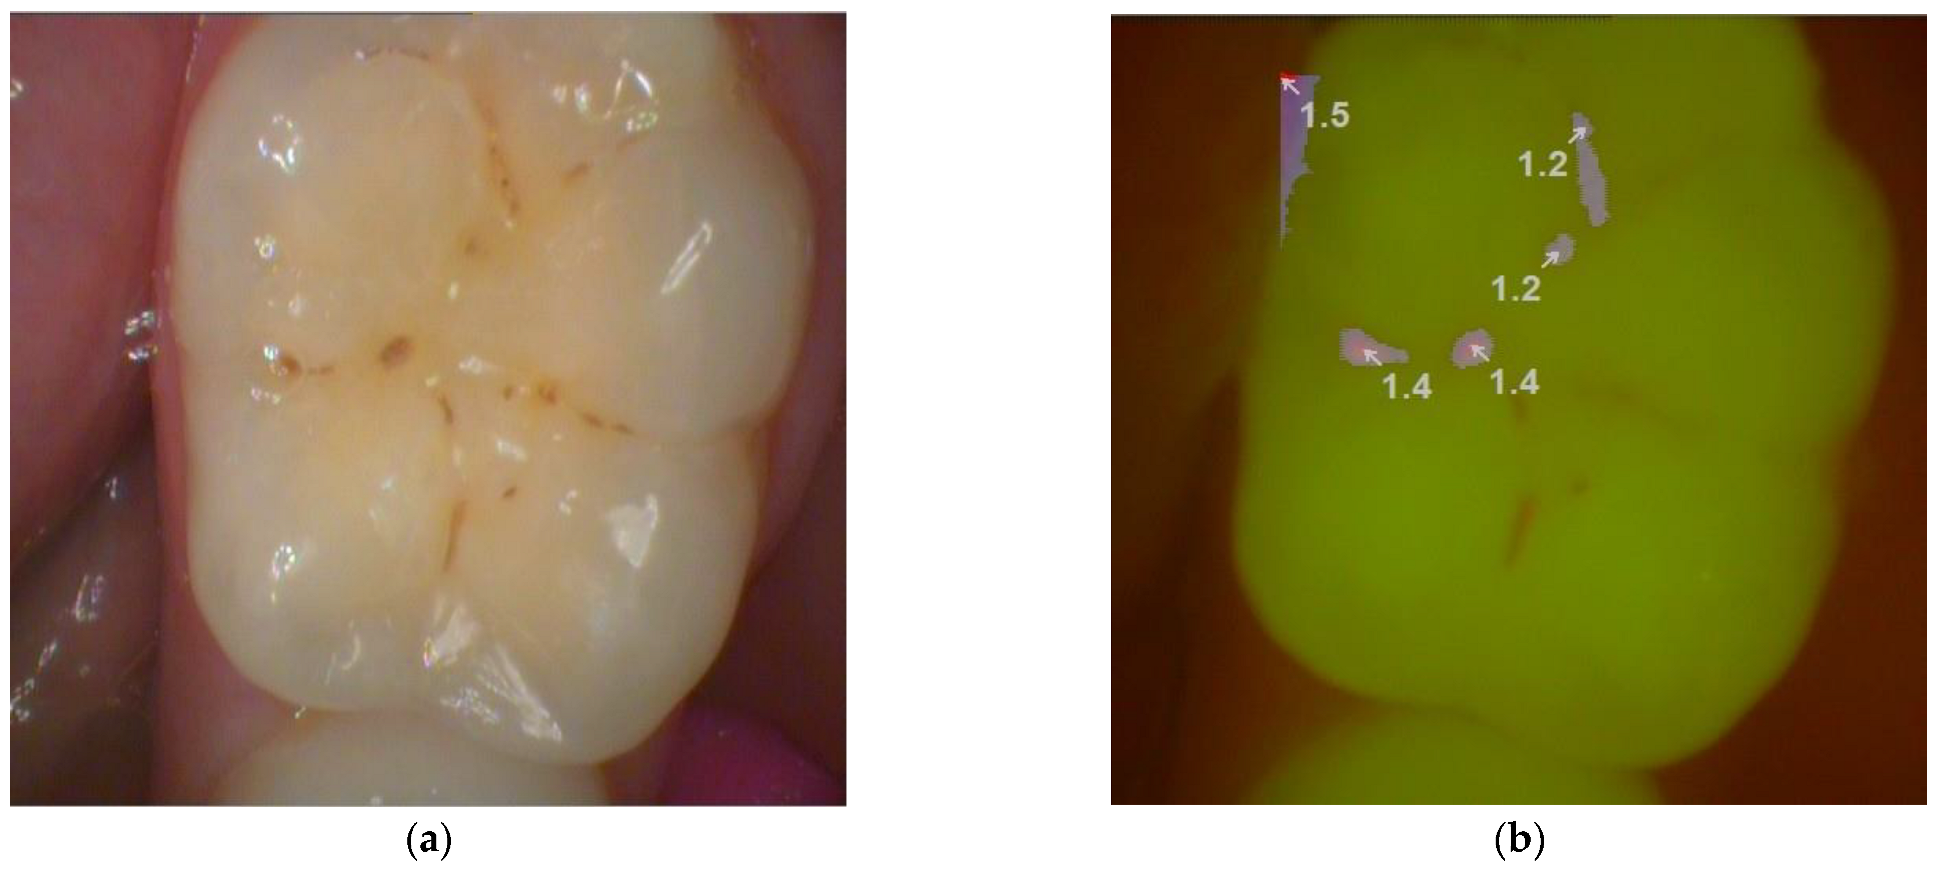

Figure 2.

Picture of a permanent molar taken by light-induced fluorescence device (a) with magnifying lens, (b) using the fluorescent mode of VistaCam iX. (Dürr Dental, Germany).